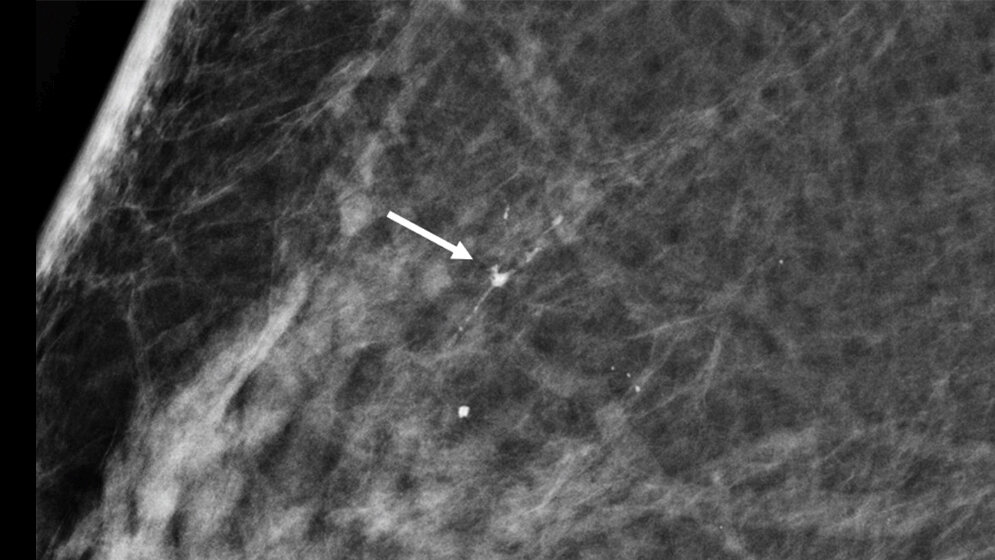

Die aktuelle Untersuchung aus Nordrhein-Westfalen hat Screening-Ergebnisse von 714.000 Frauen ausgewertet, die im Abstand von jeweils zwei Jahren bis zu dreimal am Mammographie-Screening teilgenommen haben. Bei 1.970 Frauen wurde eine Brustkrebsvorstufe entdeckt. In der Hälfte aller Fälle handelte um es sich um die aggressivste Form, wie die Folgeuntersuchungen ergaben.

Die Ergebnisse deuten auf erheblich weniger Überdiagnosen im Mammographie-Screening als oft behauptet. Bei Überdiagnosen handelt es sich um entdeckte Brustkrebserkrankungen, die im Laufe des Lebens einer Frau ohne Früherkennung nicht auffällig geworden wären. Die größte Wahrscheinlichkeit einer Überdiagnose wird den „harmlosen“ Brustkrebsvorstufen zugeschrieben, die erst in mehr als zehn Jahren in einen invasiven Brustkrebs übergehen können.

Das interdisziplinäre Forscherteam der Universität Münster hat anhand großer Datenmengen gezeigt, dass die im Folgerunden-Screening entdeckten aggressiveren Brustkrebsvorstufen schneller im Vergleich zu den harmloseren Formen nachwachsen. Daher steigt ihr Anteil mit der wiederholten Screening-Teilnahme. Das bedeutet im Umkehrschluss, dass gerade die regelmäßig teilnehmenden Frauen vom Mammographie-Screening besonders profitieren. Denn sind die Brustkrebsvorstufen aggressiv, werden sie durch diese Form der Brustkrebsfrüherkennung häufig entdeckt, bevor sie in einen aggressiven invasiven Brustkrebs übergehen können. (idw, red)